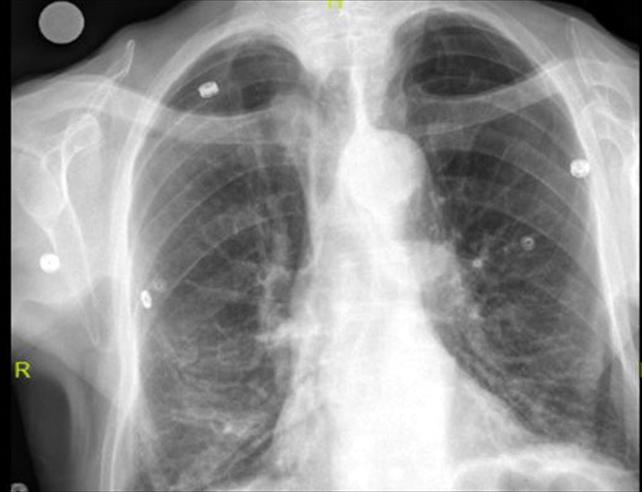

Alınan bilgiye göre, Elazığ Fethi Sekin Şehir Hastanesine öksürük ve nefes darlığı şikayetiyle başvuran 91 yaşındaki Keko Ateş'in röntgen filminde, göğsünde 10 santimetrelik çivi olduğu tespit edildi. Ateş'in soluk borusundan sağ akciğerine kaçmış olan çivi "Rijit bronkoskopi" işlemiyle çıkarıldı.

"Larenks kanseri nedeniyle 24 yıl önce larenksi (gırtlak) alınan ve boynundan nefes borusuna açılan açıklık aracılığıyla nefes alıp verebilen hastanın, nefes borusundaki bu açıklığı temizlemek amacıyla kullandığı 10 santimlik çivi, soluk borusuna kaçmış. Bunun üzerine hastamızı acil olarak ameliyata aldık. Uyguladığımız işlemi ile nefes borusundaki 10 santimetrelik çiviyi başarılı bir şekilde çıkardık. Hastamızı ameliyat sonrası bir süre serviste takip ettikten sonra sağlığına kavuşmuş bir şekilde aynı gün taburcu ettik."